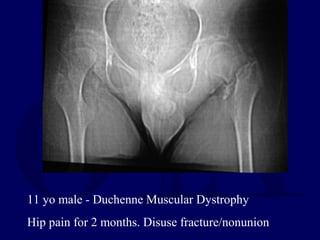

11 yo male - Duchenne Muscular Dystrophy

Hip pain for 2 months. Disuse fracture/nonunion